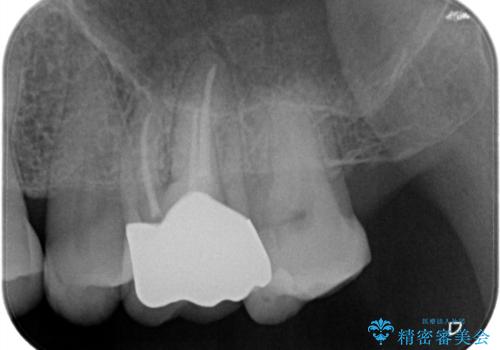

根管治療を行ったのち、症状改善を認めオールセラミッククラウンにて修復治療を行いました。

根管治療にはラバーダムシートをつけて行うことが大切です。マイクロスコープを使用し治療を行いました。治療後、歯の痛みは消失し、とても満足していただきました。

根管治療を行った歯は、再発防止や残された歯質を守るため、クラウンによる補綴治療が必要となります。